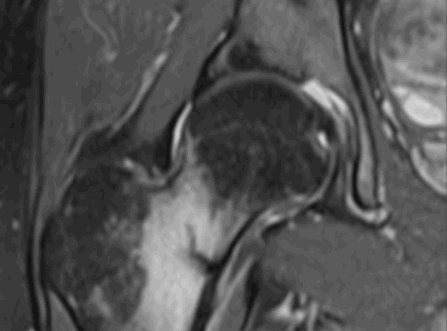

На снимке показан пример ишиофеморального импинджмента в хронической форме. Пациент - женщина в возрасте 60 лет. Жалобы - постоянные болевые ощущения в тазобедренных суставах, наиболее проявляющиеся в правом.

Гипертрофия седалищных бугристостей, ведущая к значительному сужению ишиофеморальных пространств; наблюдается деформация, отеки, несущественные скопления жидкости в квадратных бедренных мышцах (максимально заметные справа), неравномерная атрофические изменения с характерной жировой инфильтрацией.